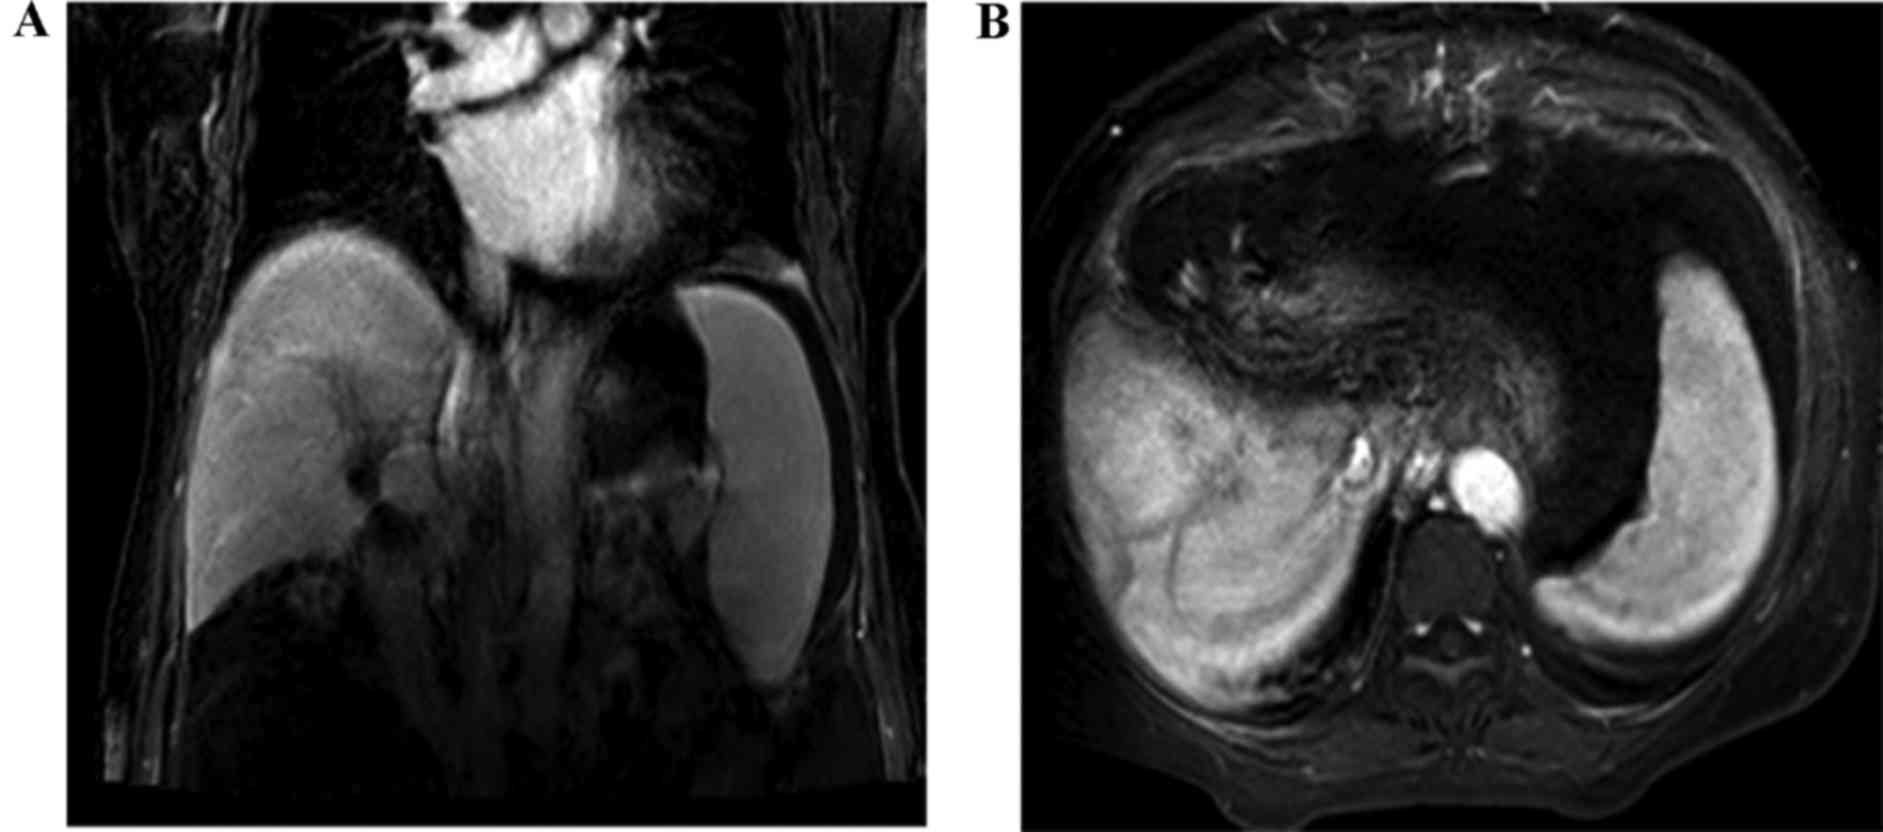

During the following-up, the level of the biomarker, CEA, was determined to be 3.2 ng/ml and the CA19-9 concentration was 32.6 U/ml 3 months after the initial radical surgery, which suggested that the patient was disease-free and that no tumor recurrence activity had been identified. The patient remained alive for 14 months without any tumors, and neither abdominal computed tomography (CT) nor a laboratory examination revealed any sign of tumor recurrence. Subsequently, the patient felt weakness of the right upper extremity and presented with mildly epigastric distention, as well as nausea, 15 months after the initial surgery. Therefore, the patient was readmitted to the Sun Yat-sen Memorial Hospital, Sun Yat-sen University, Guangzhou, China. A physical examination was unremarkable. Laboratory tests revealed that the level of aminotransferase was moderately increased, the level of CEA was 9.2 ng/ml, and the concentration of CA 19-9 was 207 U/ml. Furthermore, the cerebral MRI displayed enhancing lesions of the right subcortical frontal lobe and the left subcortical parietal cortex lobe (Fig. 2). It was clearly indicated that these small tumor entities were surrounded with flaky edema (Fig. 2B-D), which is a feature of metastatic encephaloma. Our multidisciplinary team discussed the presentation of the cerebral MRI images, and the radiologist and neurosurgeon considered that they were consistent with metastatic tumors, rather than a primary tumor of brain. At the same time, neither tumor recurrence nor locoregional lymph nodes metastasis was detected in the abdomen using contrasted CT (Fig. 3). A neurosurgeon was consulted for possible biopsy prior to chemotherapy or radiotherapy, but the patient refused to accept any further medical therapy. She died suddenly from a brain hernia due to progression of brain metastasis 2 months after the isolated brain metastasis.

Figure 3.

Results of the abdominal contrast-CT examination of the abdomen. (A and B) The abdominal contrast-CT revealed that no tumor recurrence or locoregional lymph nodes metastasis was detected 15 months after the curative resection. CT, computed tomography.